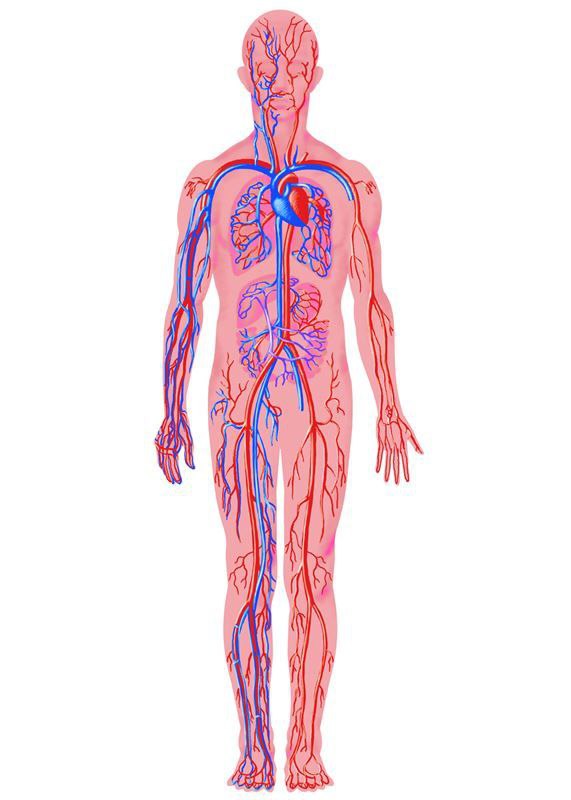

Кровеносная система человека: структура и функции

Раздел: Идеи и советы